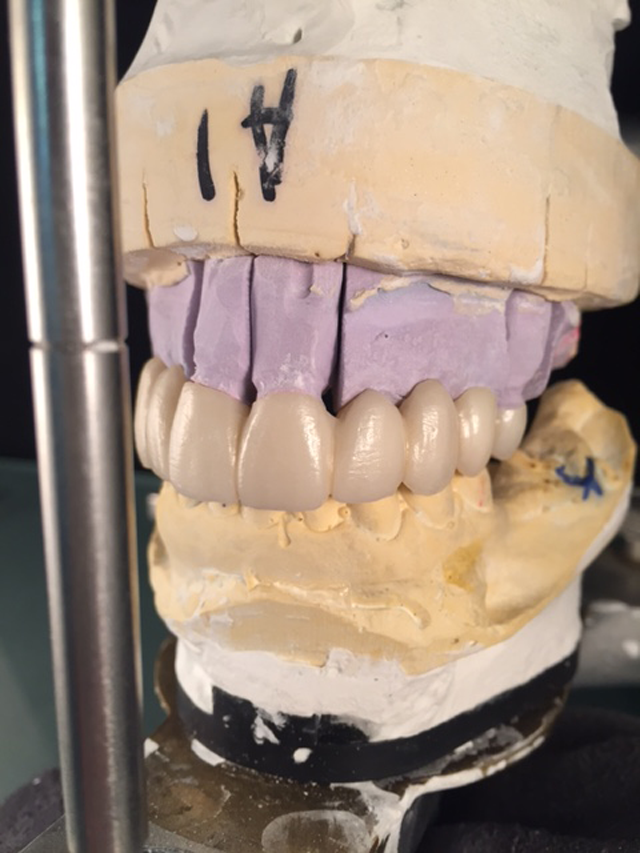

The patient no longer wanted the partial denture that she had basically learned to live with for many years; she wanted a “fixed” solution. Teeth #s 3, 4, 8, 9 and 13 were to be prepped and were our only abutments. (Figs. 1 & 2)

Fig. 1                                                                                               Fig. 2

My initial thought was to fabricate two bridges but I did not trust so few abutments and the multiple pontic spans. The doctor and I decided that a round house bridge (full upper restoration) was our best plan for success.